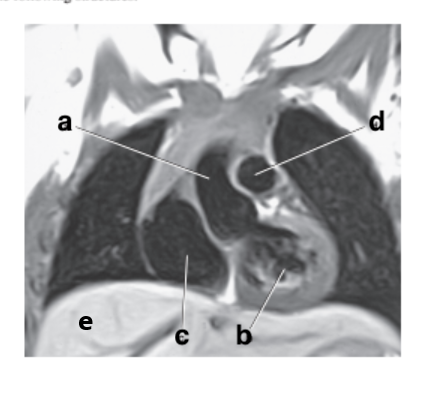

What is letter b ?

Esophagus

Which letter is the Pulmonary trunk ?

d

Which letter is the Descending aorta ?

f

Left ventricle

Which letter is the superior vena cava ?